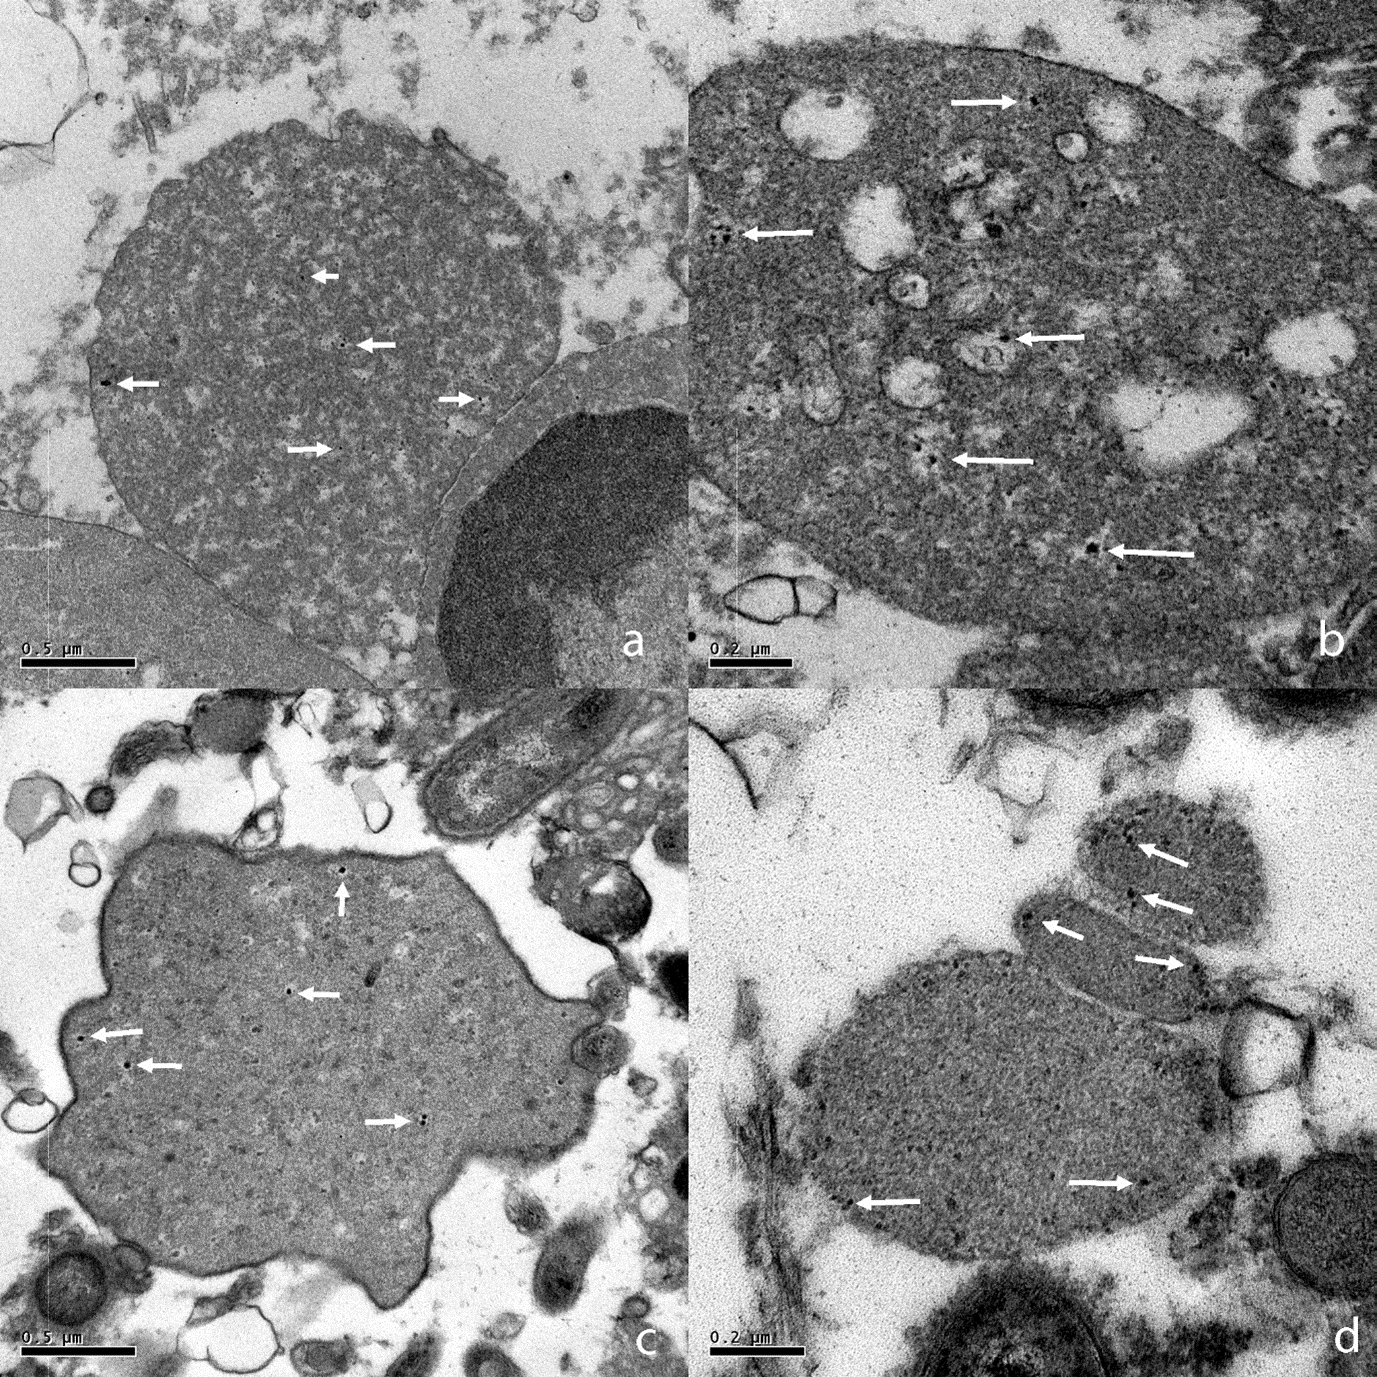

Figure 2: TEM images of CWDB from aggressive periodontitis individuals. a) CWDB with light granular cytoplasm and a small vesicle inside. 20000x. b) Vesicle at higher magnification, double layer membrane is easy visible. 80000x. c) A granulocyte containing a CWDB inside a vacuole (arrow); mag. 5000x. d) A higher magnification of the same vacuole shown in c. CWDB with lighter or darker cytoplasm can be observed inside the vacuole. 60000x. e) CWDB with dark granular cytoplasm and a well conserved plasma membrane. Light and dark small vesicles are present outside cell membrane. 50000x. f) Large CWDB (up to 5 μm) with ribosome-like granules and dark inclusions. 20000x. g) CWDB with ribosome-like granules. Light and dark small vesicles are present inside and outside cell membrane; 30000x. h) Magnification of previous image; 80000x.

In samples processed for electron microscopy, CWDB were seen only in aggressive periodontitis individuals (Figures 2a-2h) while in chronic periodontitis individuals only walled bacteria were found (Figures 6a-6d). A variety of forms were found in each aggressive periodontitis sample. Range sizes vary from 0.2 μm to 10 μm. CWDB can be recognized by the presence of the plasma membrane bi-layer and the absence of the cell wall, as shown in (Figure 2e). In some cases, these organisms presented a light granular cytoplasm with small vesicles inside, possibly representing reproductive units (Figures 2a, 2b, 2g & 2h). The presence of small ribosome-like structure was also observed (Figures 6f-6h). CWDB were found inside granulocytes, and a representative image of many pleomorphic small forms inside a vacuole is shown in (Figures 2c & 2d). Larger CWDB presented small dark and light vesicles inside the cytoplasm and some could be seen outside the membrane layer (Figures 2g & 2h).